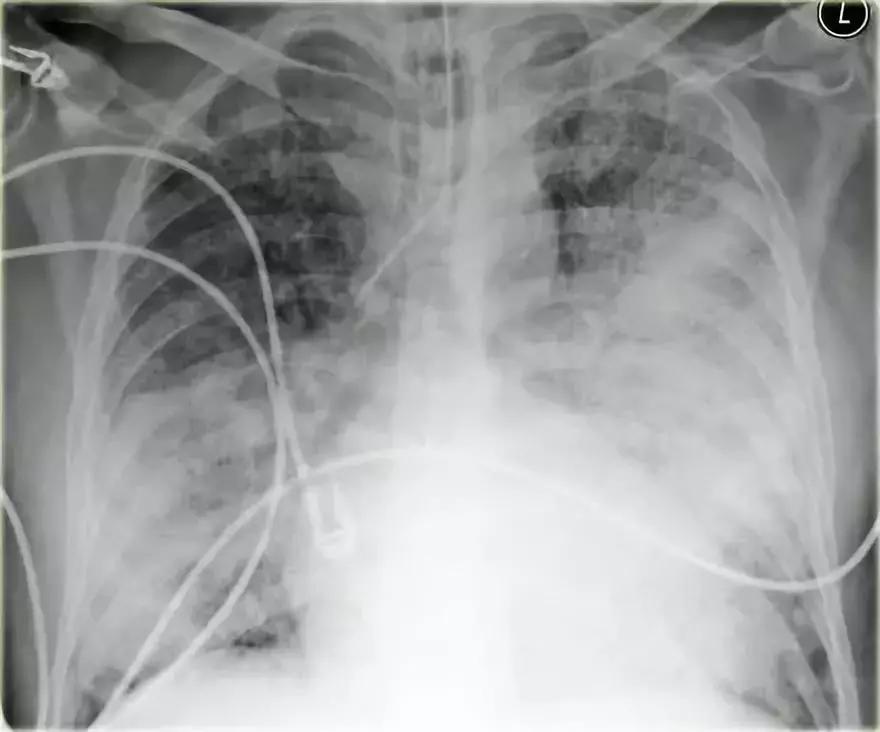

弥漫性实变

弥漫性实变最常见的原因是心源性肺水肿。心脏增大是心源性肺水肿区别于非心源性肺水肿的特征,可见其他心衰特征,如肺血流再分配、克氏B线和胸膜积液。

然而,有些心梗患者心脏大小正常,其他慢性心脏疾病为诱因的患者出现心脏增大,因合并肺感染,ARDS等,可有非心源性肺水肿。

图9 弥漫性实变

充血性心力衰竭

影像学信息:

➢ 双侧肺门实变,伴有空气-支气管征及边界模糊

➢ 心脏大小增加

➢ 间质轻微肺纹

➢ 血管蒂可能增大

图10 充血性心力衰竭